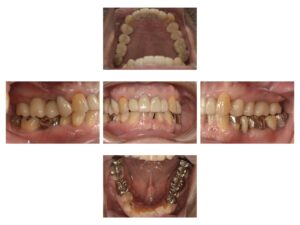

最終補綴です。咬合平面も修正されています。

今回のように、かみ合わせに問題があるケースでは治療も長期間にわたることがありますが、なるべく咬合も改善したほうがインプラントも長持ちします。